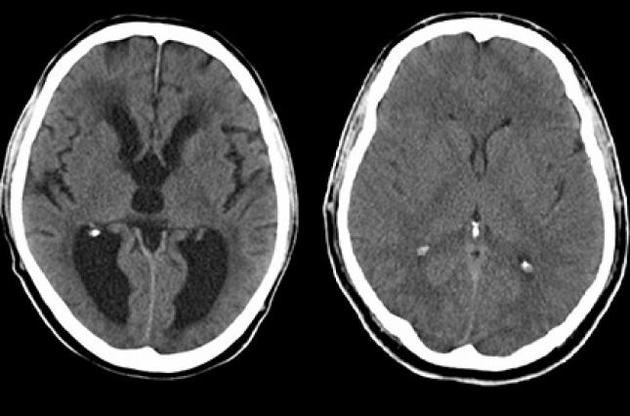

Вчені з'ясували, що відсутність SNX27 також веде до розвитку гідроцефалії у гризунів. Подальші обстеження показали відсутність епендимальных клітин, що вистилають внутрішню поверхню шлуночків головного мозку. Такі клітини забезпечують нормальну циркуляцію цереброспінальної рідини. Було встановлено, що у відсутність SNX27 мозковий стовбур виробляє надмірну кількість білка Notch, а він перешкоджає дозріванню епендимальных клітин.